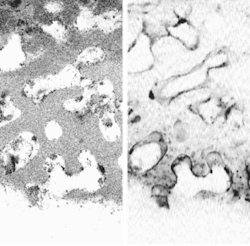

Scientists at the National Institute of Standards and Technology (NIST; Gaithersburg, MD) have combined two pre-existing imaging technologies—optical coherence microscopy (OCM) and confocal fluorescence microscopy (CFM)—whose properties complement each other for this application. Whereas OCM provides cellular images with very good rejection of light scattered out of the focal plane, and has a large (greater than 100-dB) dynamic range, CFM has relatively poor background rejection but provides crucial information on the viability of cells from fluorescence measurements.

The light source for the system's OCM segment is based on a semiconductor optical amplifier and supplies 10 mW of optical power centered on 1310 nm and with a 70-nm bandwidth. The OCM's interferometer is fiberoptic and constructed from single-mode polarization-maintaining fiber; its sensor is a coherence-domain reflectometer. Output light from the OCM segment is collimated by a free-space lens. Supplied with 488-nm light from an argon-ion laser, the CFM segment contains a photomultiplier tube for sensing. The outputs from the two systems are combined with a dichroic beamsplitter and sent through a 1.3-numerical-aperture oil-immersion objective. The systems' foci are well aligned laterally but, due to their differing wavelengths, were initially offset axially by 5 µm—a displacement later corrected optically to within 1 µm, says NIST scientist Joy Dunkers.

The OCM and CFM components can be viewed either together or separately (see figure). When cross-sectional planes of scaffolding and tissue are captured at progressively larger depths using the combined OCM and CFM information, a movie can be constructed that depicts a journey through the TEMP. The reachable imaging depth is proportional to the sample porosity and inversely proportional to the refractive-index mismatch between the scaffold and the immersion medium, explains Dunkers. For example, a partially hydrated collagen scaffold allows imaging to about 500 µm."The goal of using both OCM and CFM is to extract not only the structure of the scaffold and the location of cells using OCM, but to use the CFM as a barometer to tell us how 'happy' the cells are in the scaffold," says Dunkers. "We have fixed the cells and stained only for the presence of nuclei. We could also stain for the presence of certain proteins or extracellular matrix that is expressed to demonstrate the viability of cells. We could use a membrane stain to show us the shape of the cells. And, yes, in certain applications where we would just like to see cell migration, we may not need to stain at all and hence no CFM component is needed." Ultimately, the researchers want to characterize live cells in situ.—John Wallace